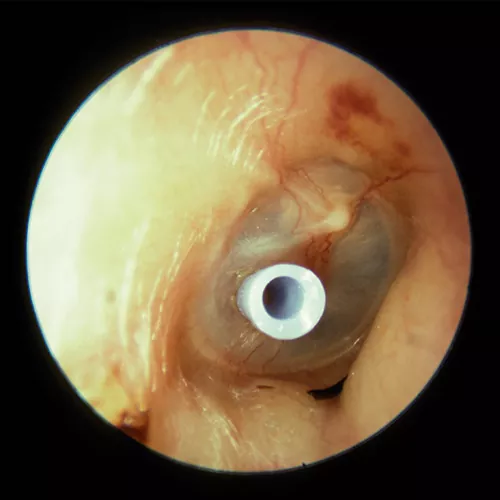

La colocación de tubos de ventilación transtimpánicos permite la ventilación del oído medio durante períodos de tiempo más prolongados. Existen distintos tipos de drenajes, los temporales, que suelen mantenerse una media de 6-12 meses y que suelen extruirse de forma espontánea, y los permanentes (tubos en T), indicados en aquellos pacientes en que es precisa la colocación de varios drenajes consecutivos por recurrencia de la clínica.

La complicación más frecuente de los drenajes es la otorrea, resultado del reflujo de secreciones desde la nasofaringe o por el desarrollo de una OMA secundaria a la entrada de agua contaminada en el oído medio a través del drenaje.

Se considera que a menor longitud del tubo de drenaje, es más probable la extrusión precoz del mismo, y a mayor longitud, existe un mayor riesgo de perforación timpánica permanente (hasta el 2% en los drenajes temporales y 17% en los permanentes).